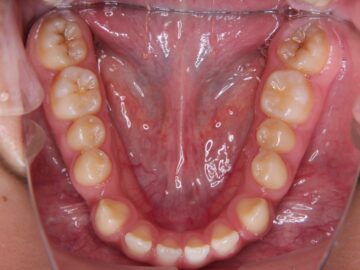

治療後